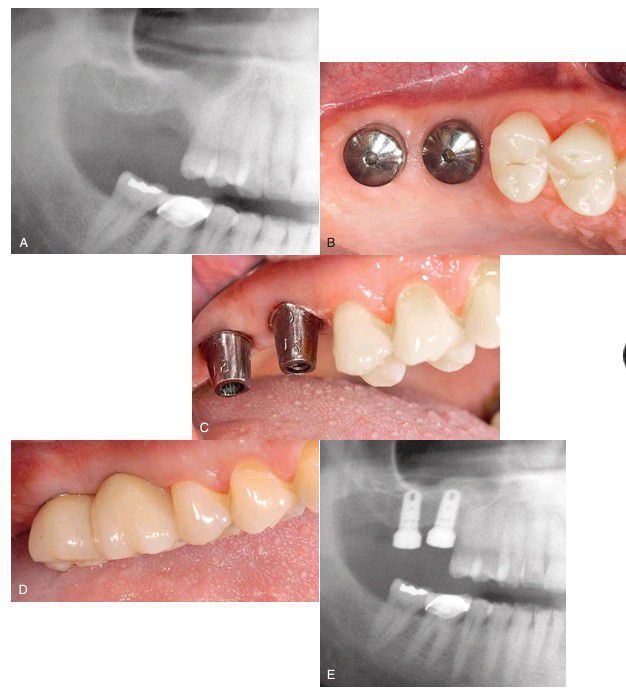

(A) Pretreatment radiograph. (B) Six months after implant placement and 3 weeks after uncovering placement of healing abutment. (C) Final abutment in place for cement-retained porcelain-fused metal (PFM) crowns. (D) Final cement-retained PFM crown restoration. (E) Final radiograph.